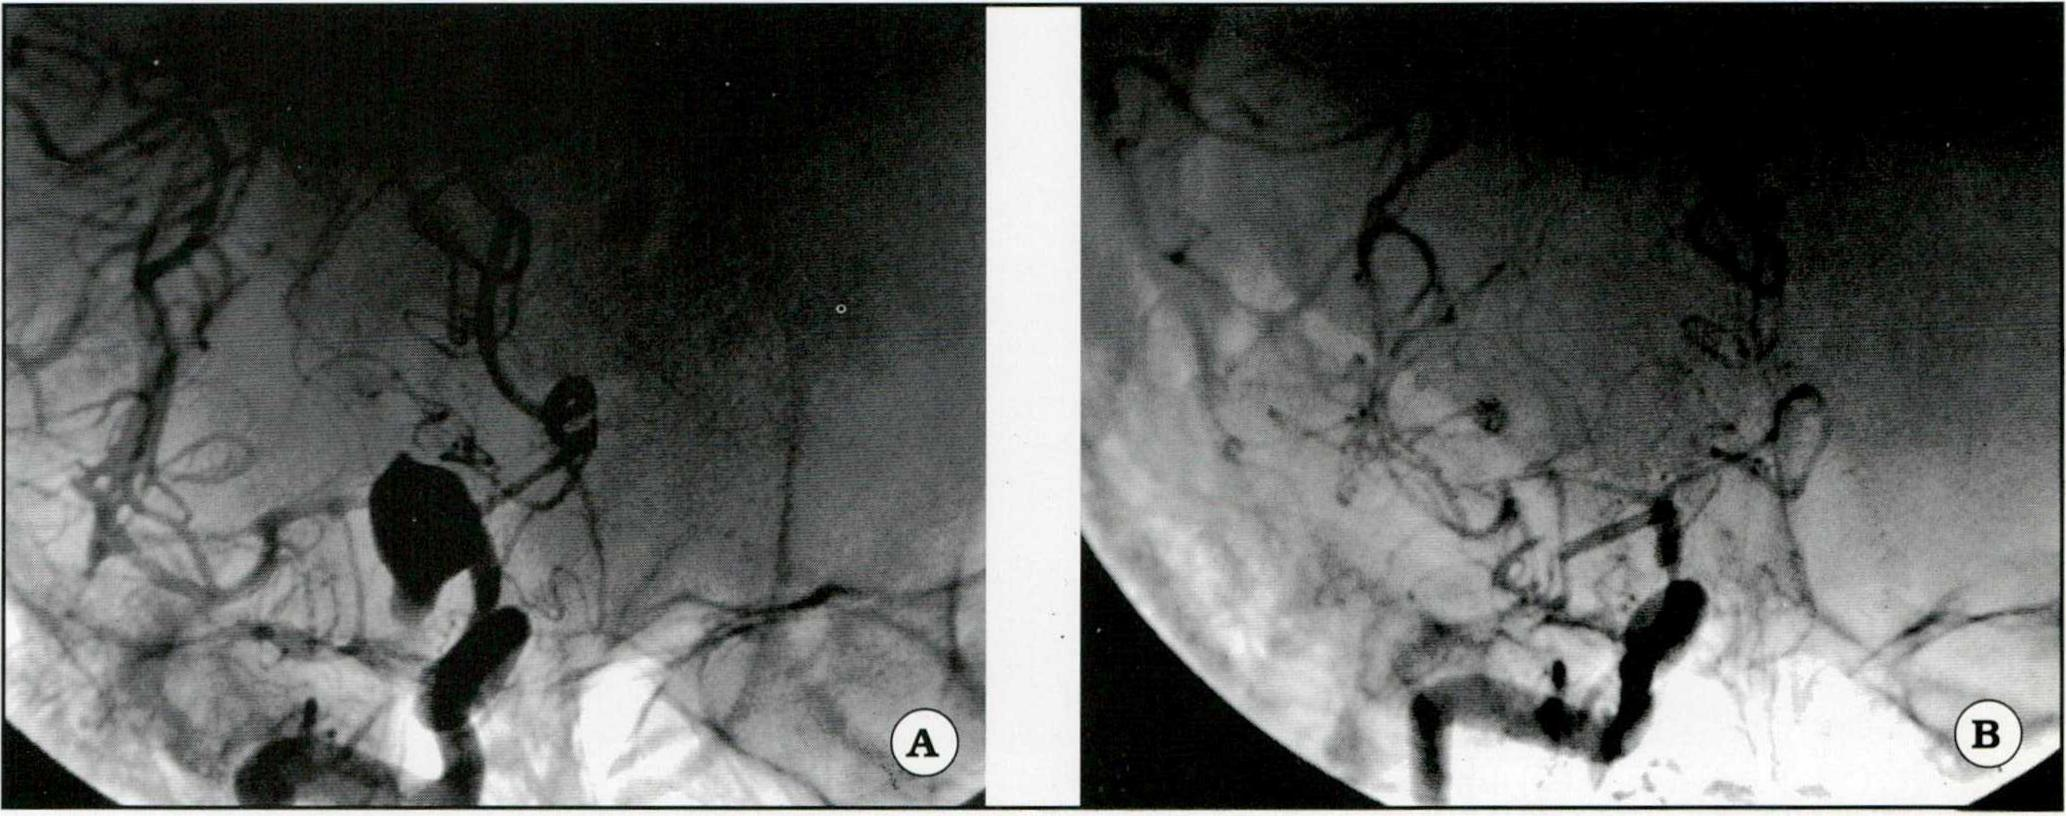

- Aneurisma gigante de la ACI ( Fig. 2).

Fig 2. A. Angiografía en posición frontal de un aneurisma carotídeo. B. Se visualiza el clipado del aneurisma con importante vasoespamoo.